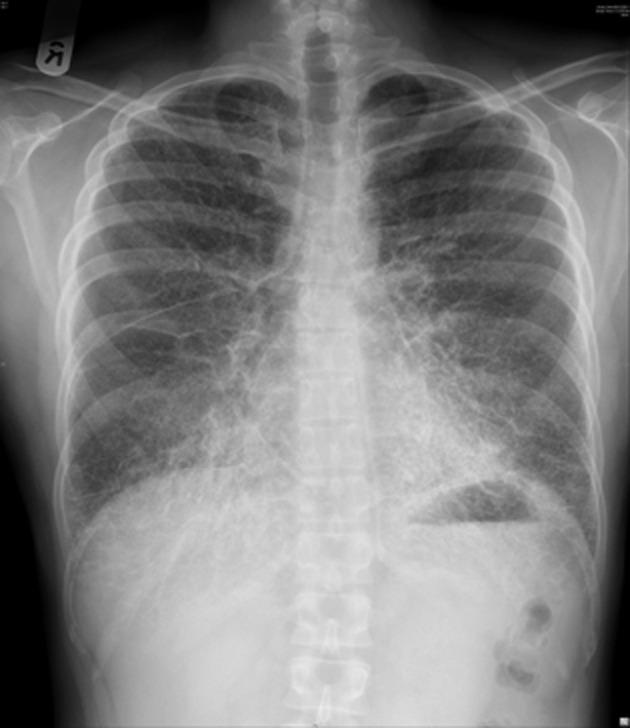

Pulmonary alveolar microlithiasis is a rare, inherited pulmonary disorder affecting young adults. Diagnosis and monitoring is important as it may progress to pulmonary fibrosis and respiratory failure. No effective treatment has been found to date.